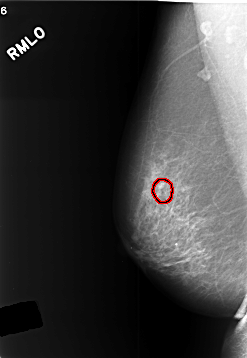

C_0412_1.RIGHT_MLO

RIGHT_MLO LINES 5720 PIXELS_PER_LINE 3952 BITS_PER_PIXEL 12 RESOLUTION 50 OVERLAY

FILE: C_0412_1.RIGHT_MLO.OVERLAY

TOTAL_ABNORMALITIES 1

ABNORMALITY 1

LESION_TYPE CALCIFICATION TYPE PLEOMORPHIC DISTRIBUTION CLUSTERED

ASSESSMENT 3

SUBTLETY 3

PATHOLOGY BENIGN

TOTAL_OUTLINES 1

BOUNDARY